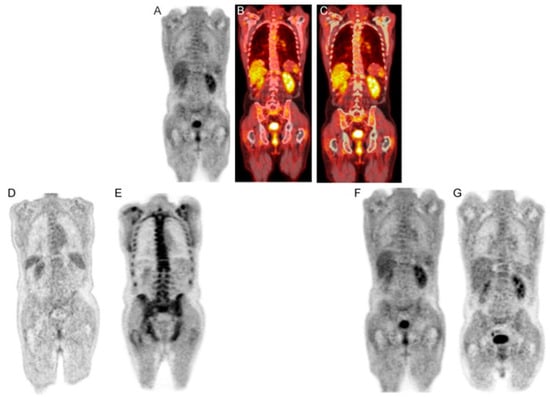

Certain research teams have recently proposed using CT-based segmentation to analyze the uptake of radiotracers in the bone marrow and the overall bone structure of myeloma patients as an alternative to concentrating solely on specific osteolytic lesions [23] (Figure 10 and Figure 11). These approaches have demonstrated a high level of reproducibility [23] (Table 1). However, the clinical significance of these methods still needs to be investigated further [23]. This method has recently been used by the Penn–Odense group to assess the uptake of [18F]FDG in the context of dual-time-point imaging (Figure 12) [35]. Pre-treatment [18F]FDG PET/CT scans from 36 patients with MM were collected [35]. These scans were conducted at 1 and 3 h after the injection of the tracer. A segmentation and quantification of whole-bone marrow (WBM) [18F]FDG uptake was performed using a threshold algorithm utilizing Hounsfield units obtained from CT data [35]. The patients were split into two treatment groups: one received non-HDT, and the other received HDT with ASCT. The international response criteria were utilized to assess the treatment outcomes for each multiple myeloma patient. In the group that underwent HDT, there was a notable increase in WBM [18F]FDG uptake among patients who responded poorly to treatment (Figure 12) [35]. The median value escalated from 1.31 (with an interquartile range, IQR, of 1.13–1.64) after one hour to 1.85 (IQR: 1.45–2.10) at the three-hour mark, illustrating this increase [35]. The calculated median percentage alteration ranged from 6.10% to 50.73% (IQR: 23.47–46.4; p = 0.003). In contrast, there was no apparent change in uptake for patients exhibiting a complete response (p = 0.24) (Figure 12). A similar pattern was observed in the non-HDT group [35].

Figure 12.

The upper row of images includes a PET scan (A), a merged PET/CT scan (B), and a combined PET/CT scan with a region of interest (ROI) applied before the use of the morphological closing algorithm (C) in a patient with multiple myeloma (MM). In the bottom row, the left-hand side images display PET scans of an MM patient classified in the poor response to treatment group, captured at 1 h (D) and 3 h (E). In this patient, the overall bone marrow [18F]FDG uptake escalated from 0.89 (D) to 2.31 (E), reflecting a percentage change of 158.15%. On the right-hand side of the bottom row, the images present PET scans of an MM patient from the complete response group, taken at 1 h (F) and 3 h (G). In this patient, there was a slight reduction in the overall bone marrow [18F]FDG uptake, dropping from 0.83 (F) to 0.82 (G), with a percentage change of −0.79%. Note that the second decimal number is rounded up. PMID: 33224622, PMCID: PMC7675111, Free Access.